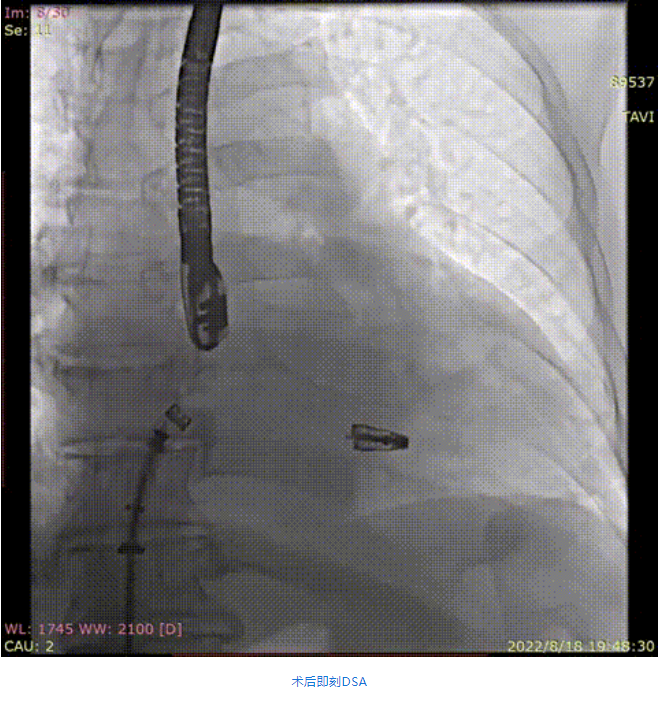

手術采用全身麻醉插管,經股靜脈-房間隔入路,在TEE和DSA引導下完成房間隔穿刺。置入瓣膜夾系統后,在左房調整瓣膜夾的位置和軸向,后進入左室,在TEE引導下捕捉二尖瓣前后瓣葉,并關閉瓣膜夾。經TEE反復確認手術效果后最終鎖定并釋放瓣膜夾。術后即刻超聲顯示瓣膜夾位置穩定,功能良好,肺靜脈逆流和左房壓都明顯好轉。